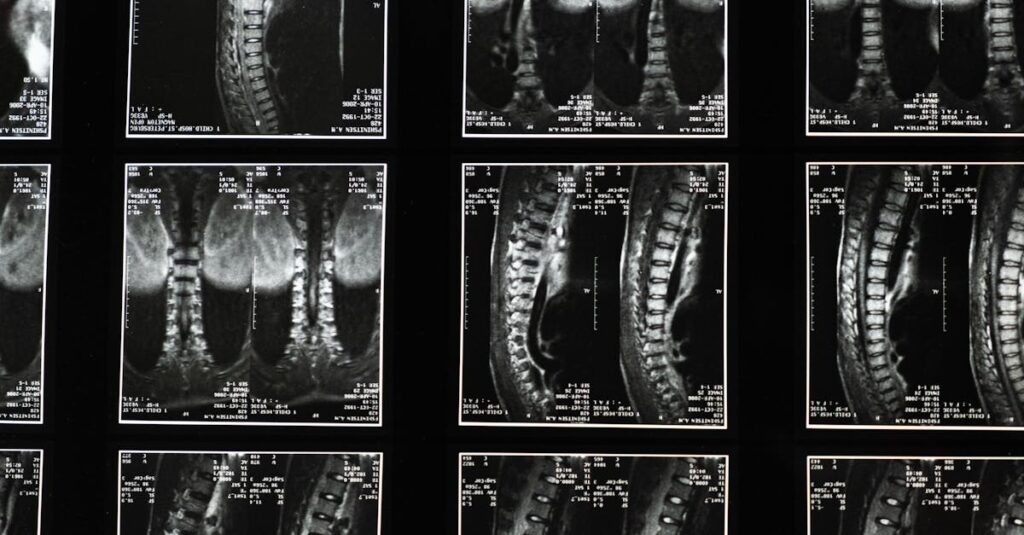

Quels examens permettent de diagnostiquer une protrusion discale?

Une IRM ou une radiographie est souvent nécessaire pour confirmer le diagnostic d’une protrusion discale.